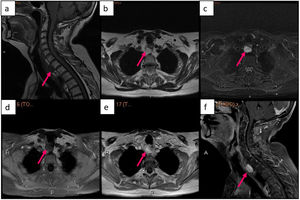

The diagnosis of PHP is made by means of an adequate clinical history together with a measurement of calcium corrected by albumin and PTH in serum, and the only effective treatment is surgery. Classically, surgery consisted of a bilateral exploration of the neck and excision of the affected glands,4 but the fact that the majority of PHP cases are due to disease of a single gland, together with the improvement of intraoperative monitoring of PTH and preoperative localization using imaging studies have favoured the development of minimally invasive parathyroidectomy.2,7 This latter modality has similar cure rates to bilateral surgical exploration, with similar recurrence, persistence, and reoperation rates. However, by minimising tissue dissection, it speeds up recovery time, reduces postoperative pain, and decreases scarring (and therefore leads to better aesthetic results), as well as having lower cost and less complications. In addition, bilateral surgical exploration requires hospital admission, while unilateral surgery is an outpatient procedure, thus it has been established as a safe and effective method.8–11 The success of minimally invasive surgery undoubtedly depends on the experience of the surgeon,1 but also on the precise pre-surgical localisation of the affected parathyroid gland, including not only lateralization but also the quadrant specifically.12 However, locating the pathological parathyroid by means of imaging techniques is frequently problematic due to the anatomical variants that these glands can present, especially the inferior ones due to their more prolonged embryological migration.8 In fact, approximately 16% of cases have one or more hyperfunctioning parathyroids in an ectopic location3 (Figs. 1–6).

Figure 1.

Left inferior parathyroid adenoma observed in scintigraphy. (a) 99mTc-sestaMIBI scintigraphy in early phase, (b) planar scintigraphy in late phase, (c) SPECT in early phase, (d) SPECT in phase late, (e) CT and (f) SPECT-CT. Obtained from a patient at our hospital.